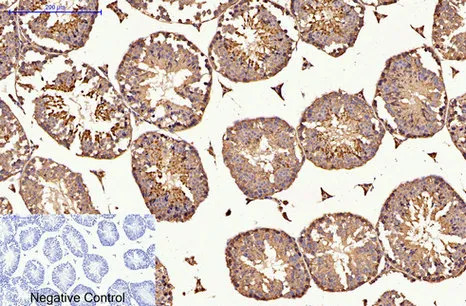

CDX2(14H6)Mouse Monoclonal Antibody

Cat: AMM08595

Size1:50μL Price1:$118

Size2:100μL Price2:$220

Size3:200μL Price3:$380

Application:WB,IF-P,IF-F,ICC/IF,IHC-P

Reactivity:Human,Mouse,Rat

Conjugate:Unconjugated

Optional conjugates: Biotin, FITC (free of charge). See other 26 conjugates.

Gene Name:CDX2